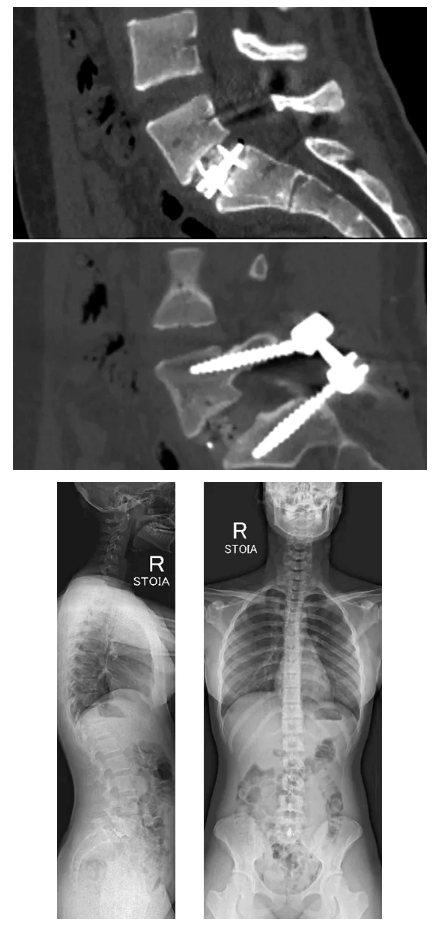

Операцию проводили руководитель Клиники патологии позвоночника и редких заболеваний, к.м.н. Алексей Евсюков и врач-вертебролог отделения №9, к.м.н. Полина Очирова. Вмешательство выполнили в два этап. Первым выполнили передний спондилодез, установили кейдж. Вторым этапом выполнили транскутанный спондилосинтез с последующей фиксацией.

Сейчас 18-летняя пациентка чувствует себя хорошо, боли купированы, девочка проходит реабилитацию.